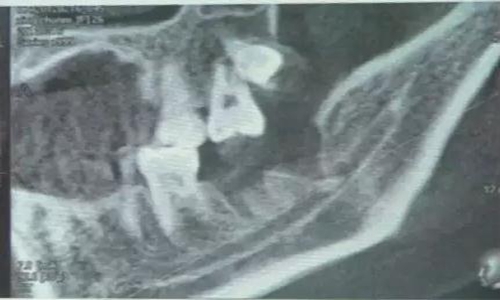

下面看一個病例,患者,女,30歲,因左下頜智齒嵌塞食物后疼痛,至當(dāng)?shù)匮揽平o予拔除,但術(shù)后1個半月,患者自覺拔牙區(qū)一直隱隱疼痛,時輕時重,遂來診。檢查發(fā)現(xiàn),拔牙創(chuàng)口一直未愈合,未見明顯腫脹,拍片發(fā)現(xiàn),拔牙窩內(nèi)顯示高密度斷根影

像,該斷根臨近下頜神經(jīng)管,同時發(fā)現(xiàn)第二磨牙遠中有兩塊高密度影像,疑似殘留骨片或牙片,應(yīng)該是引起疼痛的原因,經(jīng)與患者溝通,采納建議,進行二次拔牙。

用到4號牙挺,避免敲擊拔牙根,稍有不慎,可能會出現(xiàn)牙根移位下頜神經(jīng)管。